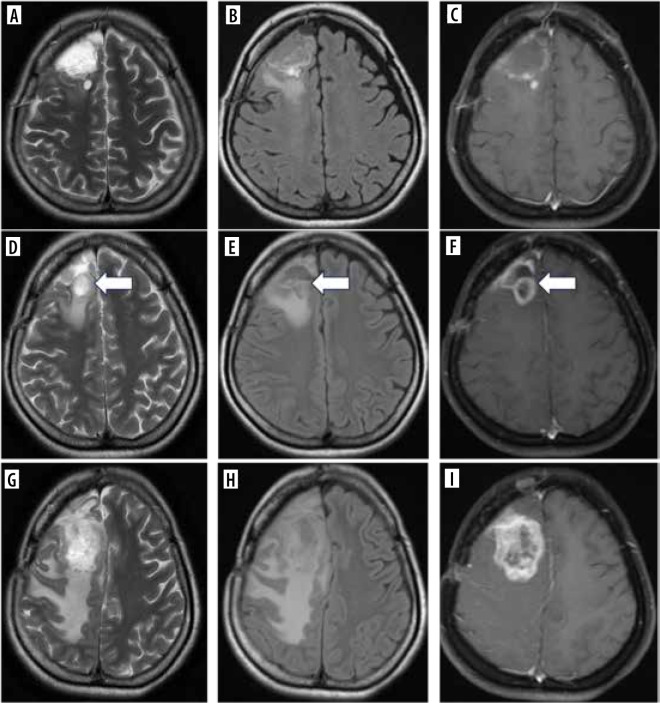

Purpose: To independently and externally validate the Brain Tumour Reporting and Data System (BT-RADS) for post-treatment gliomas and assess interobserver variability.

Material and methods: In this retrospective observational study, consecutive MRIs of 100 post-treatment glioma patients were reviewed by two independent radiologists (RD1 and RD2) and assigned a BT-RADS score. Inter-observer agreement statistics were determined by kappa statistics. The BT-RADS-linked management recommendations per score were compared with the multidisciplinary meeting (MDM) decisions.

Results: The overall agreement rate between RD1 and RD2 was 62.7% (κ = 0.67). The agreement rate between RD1 and consensus was 83.3% (κ = 0.85), while the agreement between RD2 and consensus was 69.3% (κ = 0.79). Among the radiologists, agreement was highest for score 2 and lowest for score 3b. There was a 97.9% agreement between BT-RADS-linked management recommendations and MDM decisions.

Conclusions: BT-RADS scoring led to improved consistency, and standardised language in the structured MRI reporting of post-treatment brain tumours. It demonstrated good overall agreement among the reporting radiologists at both extremes; however, variation rates increased in the middle part of the spectrum. The interpretation categories linked to management decisions showed a near-perfect match with MDM decisions.